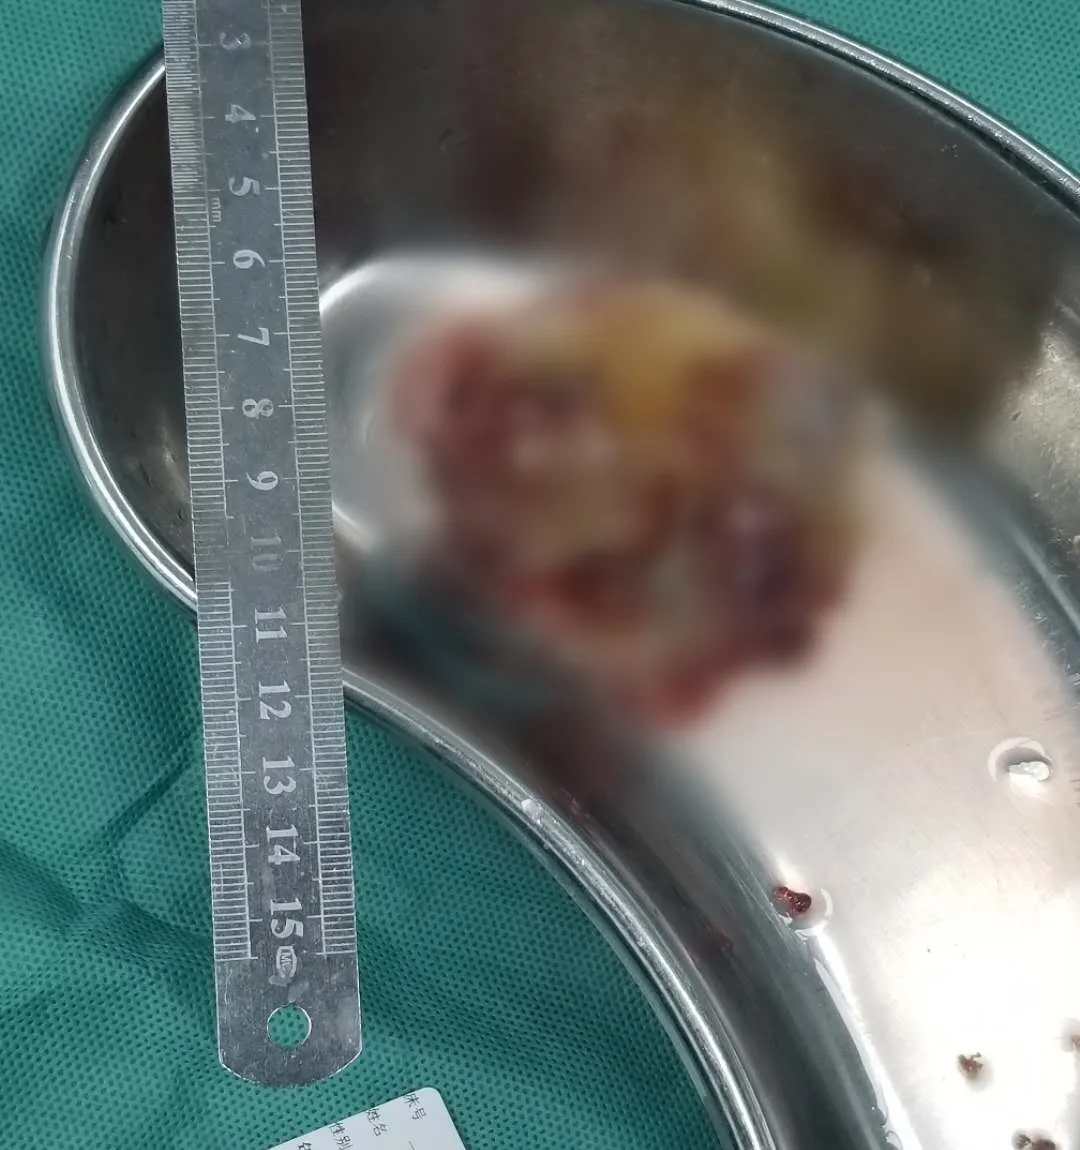

经术中探查,老人的粘液瘤直径足有近6厘米,满满地填塞在心房内,呈暗褐色胶冻样。由于肿瘤异常松软,轻微的触碰都可能导致瘤体破裂,增加栓塞的危险性。在多方协作下,林智率团队沿着瘤蒂附着处细致操作,最终在3个多小时手术后,完整地切除了整个肿瘤。